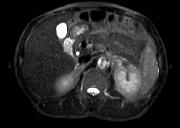

问题 男,52岁,下肢无力伴多饮多尿2 年余,实验室检查:低血钾,血醛固酮水平及24h 尿醛固酮定量超过正常值,MRI检查如图所示,应诊断为 ( )

选项 A、左肾上腺髓脂瘤 B、左肾上腺转移瘤 C、左肾上腺腺瘤 D、左肾上腺嗜铬细胞瘤 E、左肾上腺囊肿

答案 C